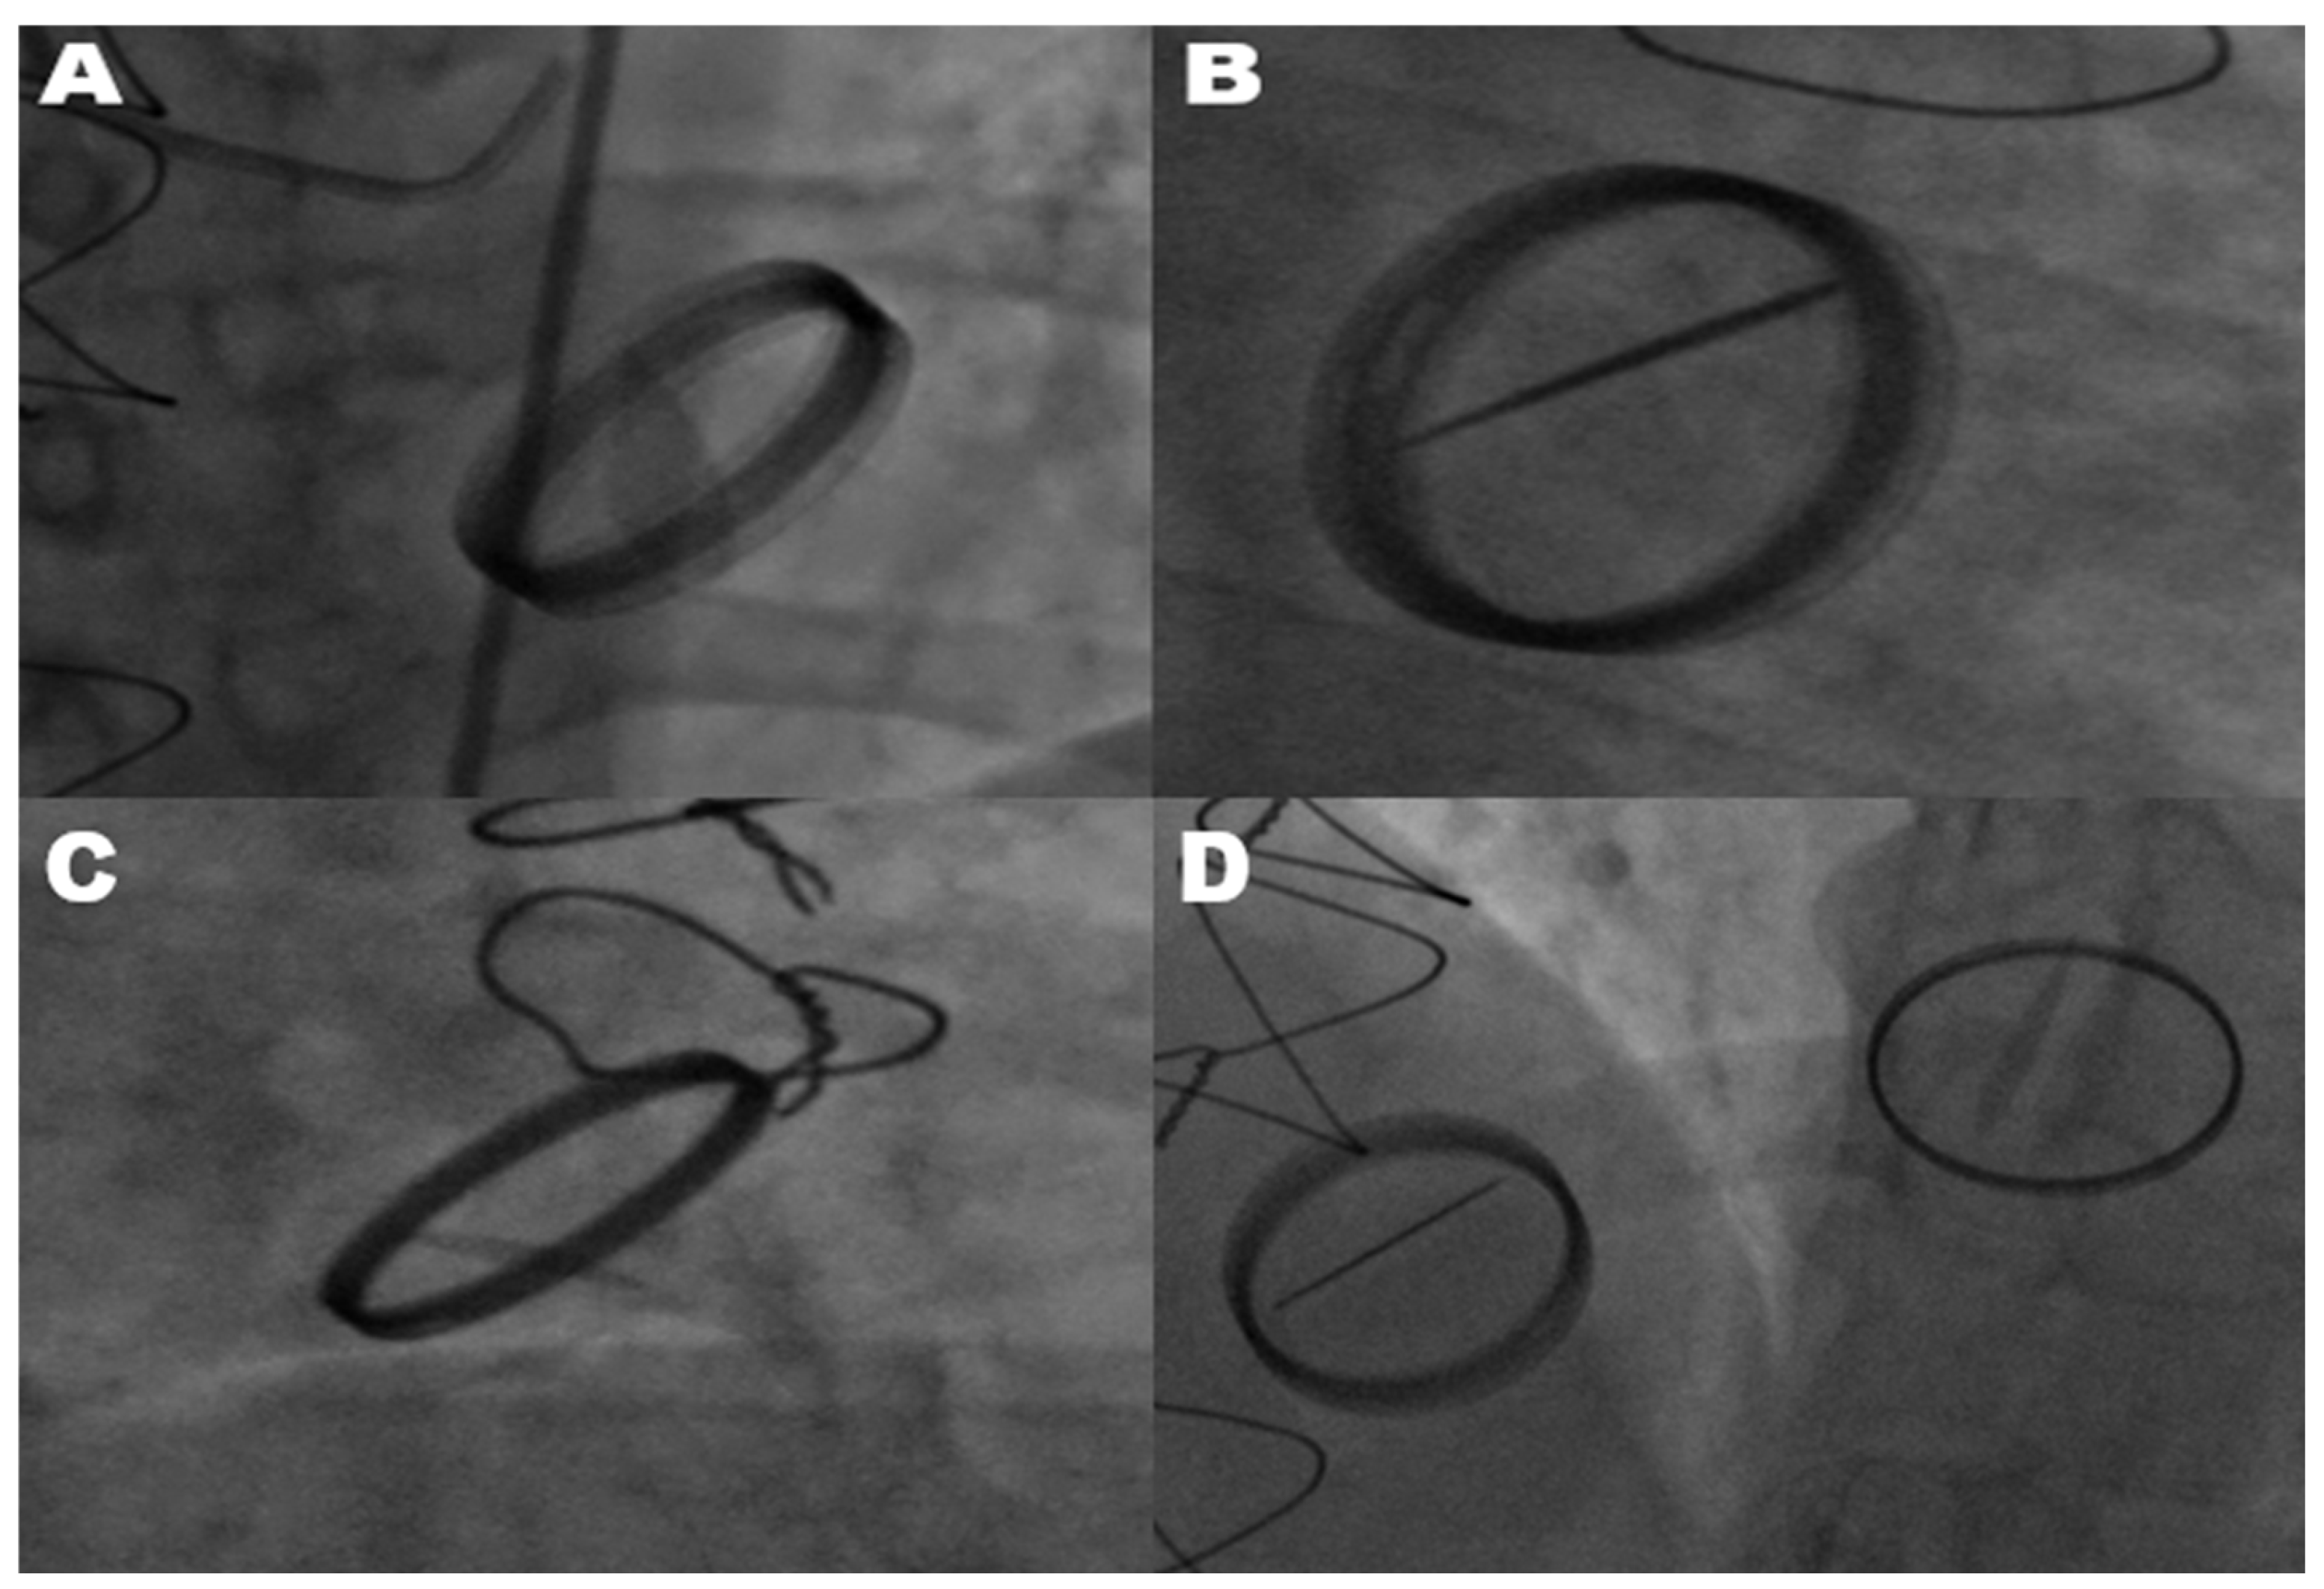

The diagnosis of mechanical prosthetic valve dysfunction, specifically a stuck valve, was confirmed through the combined use of transthoracic echocardiography and fluoroscopy. Transthoracic echocardiography was employed as the primary modality to evaluate leaflet mobility, detect the presence of thrombus or pannus, and assess associated hemodynamic alterations. Fluoroscopy complemented echocardiographic findings by directly visualizing the mechanical motion of valve leaflets. In cases where only one leaflet demonstrated motion, fluoroscopy reliably identified restricted leaflet mobility, confirming a stuck valve diagnosis. Echocardiography and fluoroscopy, when used in tandem, significantly improved the diagnostic accuracy of stuck valve identification and minimized the risk of misdiagnosis. This two-tiered assessment approach ensured the reliability of the diagnosis, enabling clinicians to proceed with surgical intervention despite the elevated operative risks associated with reoperation. All mechanical valves included in this study were bileaflet prosthetic valves, as verified through surgical and echocardiographic records. This uniformity in valve type minimized the variability stemming from differences in valve design, ensuring the study’s focus on pannus formation and hemodynamic gradients remained consistent. As shown in Figure 1, fluoroscopic imaging highlights the hallmark feature of limited leaflet motion in bileaflet metallic valves. This restriction in leaflet mobility significantly impairs hemodynamic function and was observed across various valve positions, including the mitral, aortic, and tricuspid valves.

Figure 1.

Fluoroscopic images of restricted leaflet movement in stuck prosthetic valves. This figure shows a fluoroscopic assessment of restricted leaflet movement in stuck metallic bileaflet mitral, aortic, and tricuspid valves, likely due to the mechanical obstruction caused by pannus. (A) Shows the mitral valve in a partially open position, with only one leaflet exhibiting movement, indicating a significant obstruction affecting valve function. (B) Depicts the mitral valve in an open position, with one leaflet remaining immobile, further demonstrating a mechanical limitation likely due to pannus. (C) Illustrates a stuck bileaflet metallic aortic valve, where the restricted leaflet movement suggests interference at the valve plane. (D) Displays a patient with previous metallic bileaflet mitral valve replacement and tricuspid valve replacement. In this view, only one leaflet of the stuck tricuspid valve is moving, highlighting that there is also an obstruction in the tricuspid valve. Additionally, the metallic bileaflet mitral valve is functioning normally, with both leaflets opening fully.